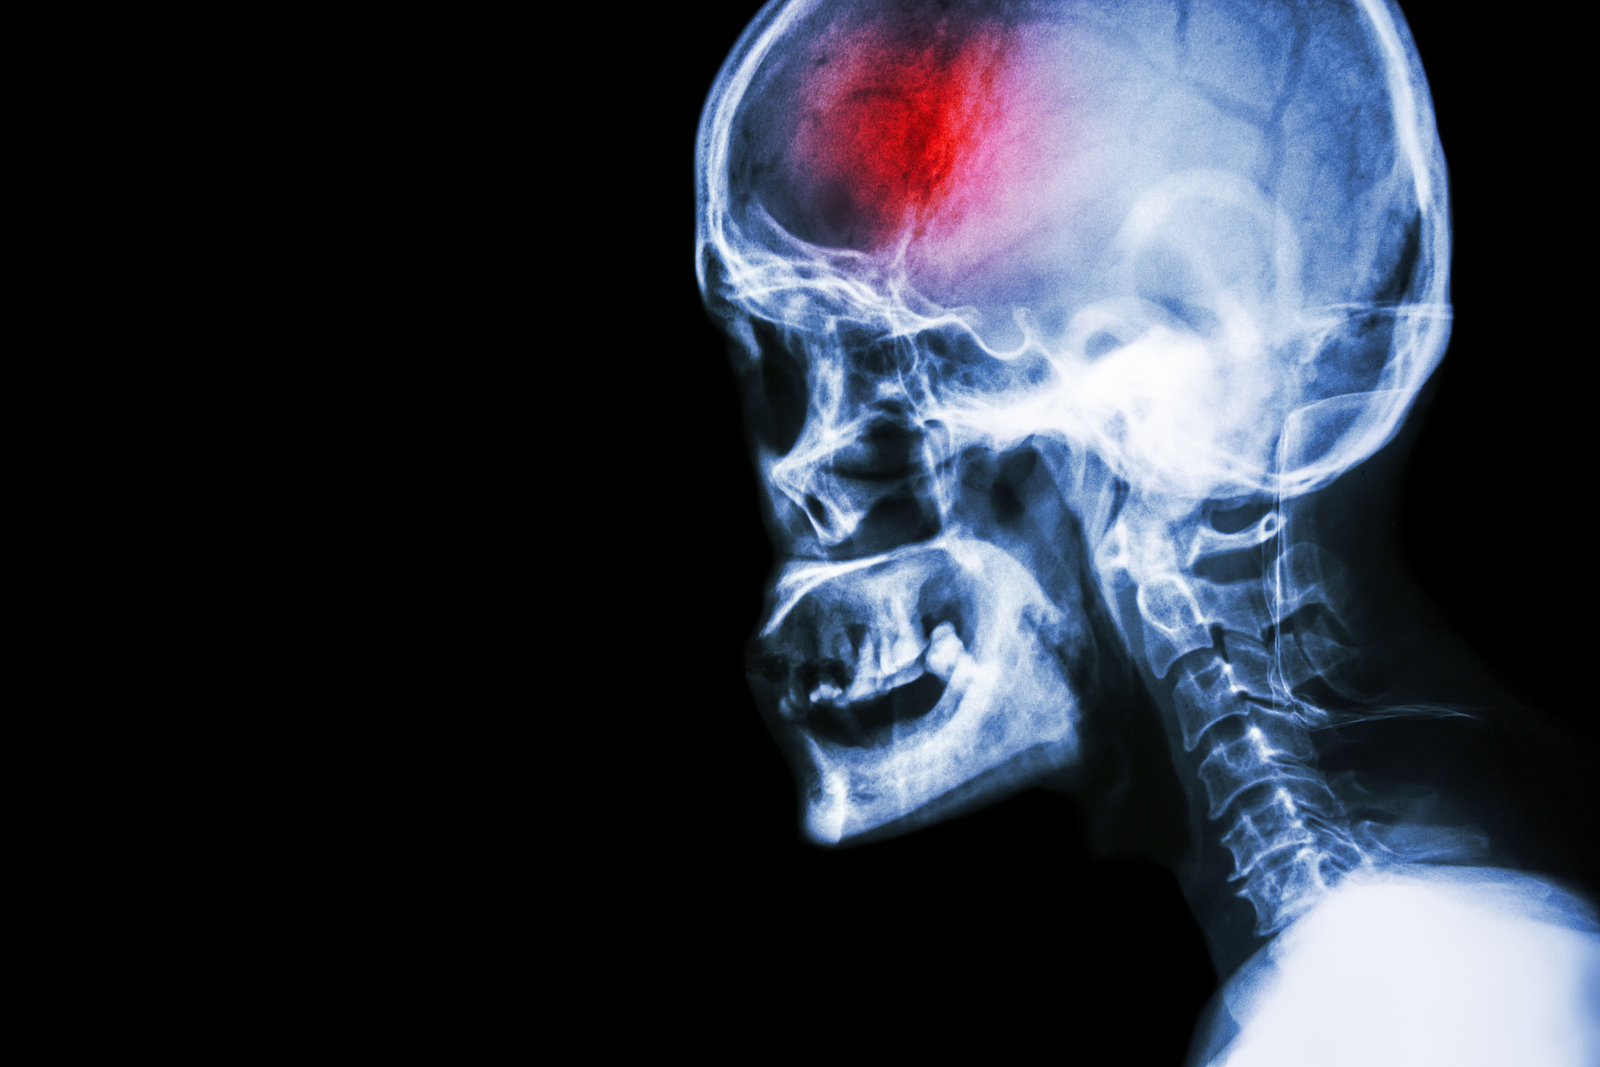

A stroke (previously known as a cerebrovascular accident) when there is a decreased flow of blood to the brain from either a blockage in the blood vessels that supply the brain (ischemic stroke), or a bleed from the blood vessels that supply the brain (hemorrhagic stroke). When the blood flow to the brain is blocked it prevents the brain from getting the needed oxygen and nutrients to function. Without oxygen the brain cells can be permanently damaged or die and the physical and mental functions related to that area of the brain will be affected. A stroke is a medical emergency and rapid treatment is crucial to decreasing the damage caused by a stroke.

Computed Tomography (CT) scan and/or Magnetic Resonance Imaging (MRI) scan: These tests are done on your brain and used to locate the exact location of the stroke and to determine if it has been caused by a blockage or a bleed. These tests can also help rule out other conditions that may be causing symptoms, such as an infection or a brain tumour

The effects of each stroke are unique depending on where the blockage or bleed occurs within the brain. The brain anatomy is similar in all individuals, so if a stroke occurs in the left side of the brain, the function of the right side of the body will be affected. If a stroke occurs in the right side of the brain, the left side of the body will be affected. If one side of the body is fully paralyzed, it is called hemiplegia. If one side of the body is only partially affected and shows weakness rather than paralysis, it is called hemiparesis.